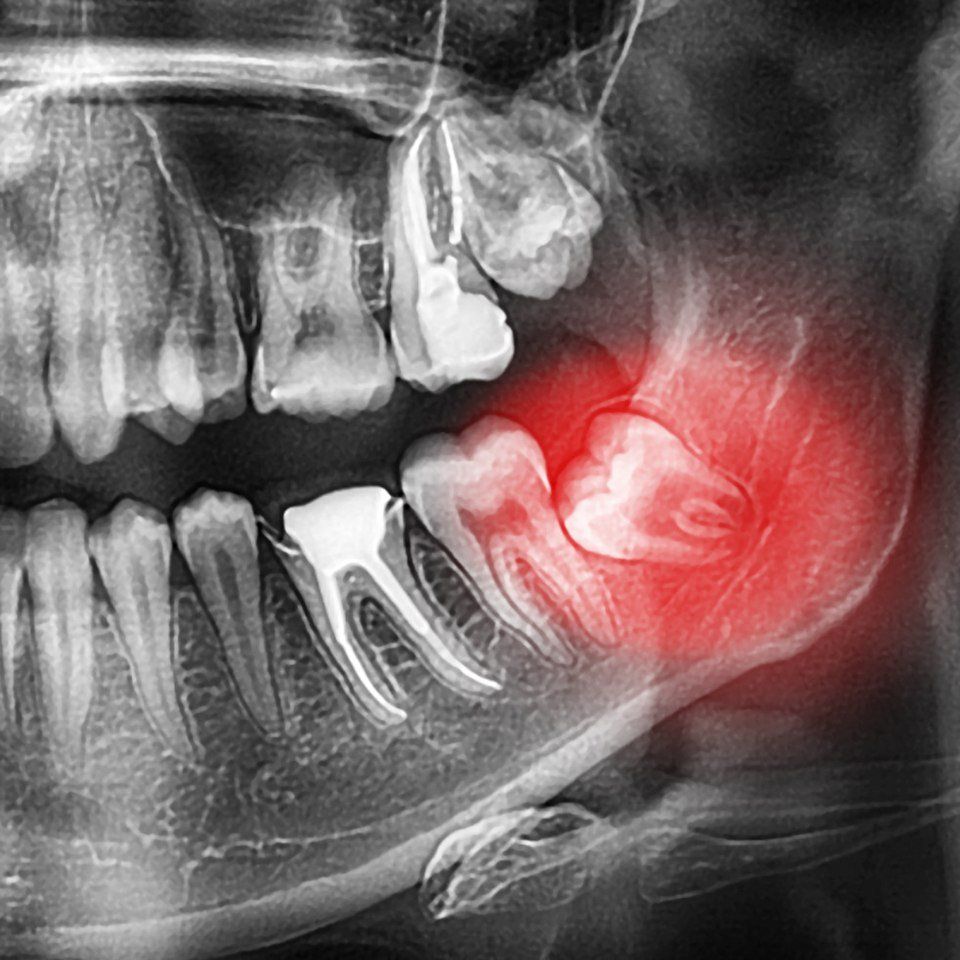

Il dente che più frequentemente rimane “ritenuto” all’interno dell’osso è il dente del giudizio, che nasce per ultimo e che per questo motivo spesso non “trova” più uno spazio utile alla sua eruzione. Dopo di questo altro dente che talvolta non erompe e rimane incluso è il canino, soprattutto nell’arcata superiore. L’estrazione di “inclusi” è manovra chirurgica molto delicata che deve essere eseguita con elevata perizia per la vicinanza di strutture nobili vascolari e nervose che vanno assolutamente preservate.

Presso lo studio dentistico del Dr. Massimo Fagnani di Lucca il personale medico odontoiatrico esegue interventi di chirurgia estrattiva come quello per la cura del dente del giudizio. Nei casi in cui non sia possibile preservare un dente nel cavo orale del paziente, nemmeno attraverso la sinergia fra le varie specialità, si procederà con la sua rimozione. Questo procedimento avviene soprattutto nei casi di denti del giudizio inclusi, radici ormai prive di funzionalità, germi dentali, altri denti inclusi la cui eruzione è ormai impossibile e dannosa per le altre strutture orali.